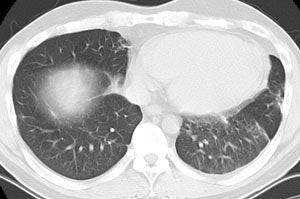

Open lung biopsy confirmed the diagnosis of BOOP. Following institution of therapy with steroids the lung lesions resolved. Click images to enlarge.